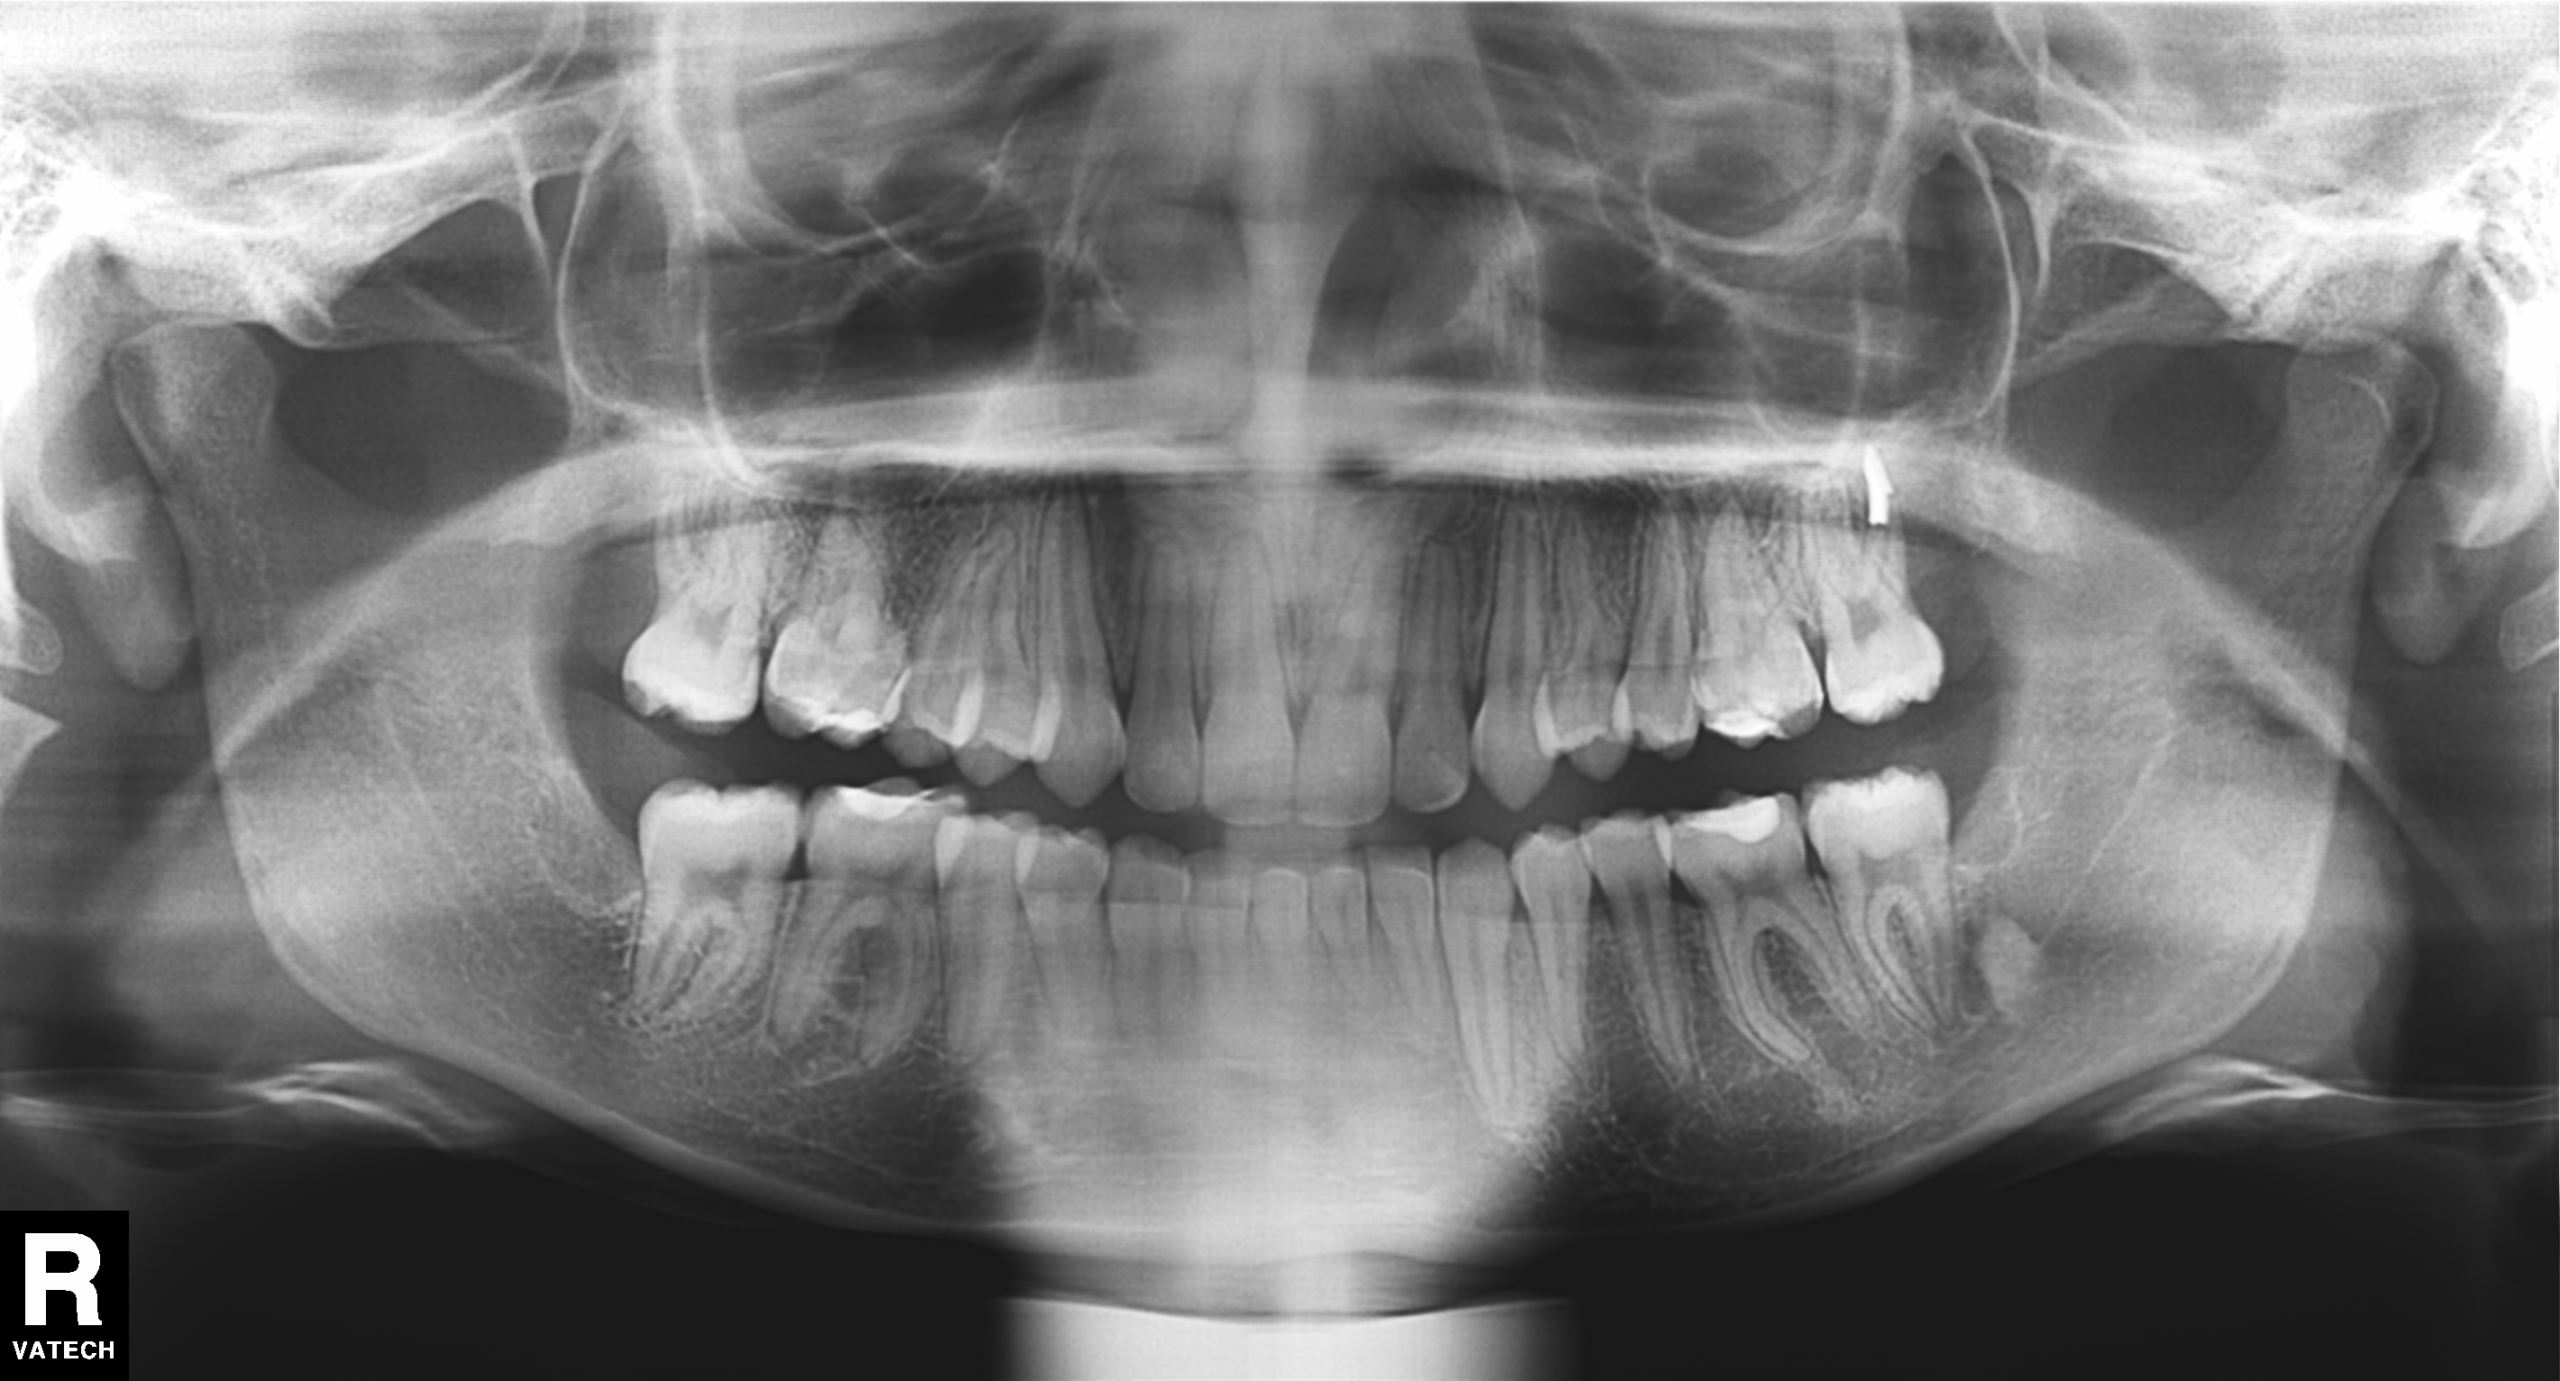

En la Ortopantomografía se observa una Curva de Spee inferior muy acentuada y los 4 cordales en formación.